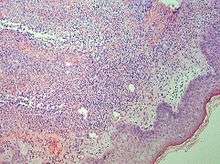

Punch biopsy of a skin lesion showing neutrophilic infiltration in the dermis, with no evidence of vasculitis (same patient with Crohn's disease).

Studies show a moderate neutrophilia (less than 50%), elevated ESR (greater than 30 mm/h) (90%), and a slight increase in alkaline phosphatase (83%). Skin biopsy shows a papillary and mid-dermal mixed infiltrate of polymorphonuclear leukocytes with nuclear fragmentation and histiocytic cells. The infiltrate is predominantly perivascular with endothelial-cell swelling in some vessels, but vasculitic changes (thrombosis; deposition of fibrin, complement, or immunoglobulins within the vessel walls; red blood cell extravasation;inflammatory infiltration of vascular walls) are absent in early lesions.

Perivasculitis occurs secondarily, because of cytokines released by the lesional neutrophils. True transmural vasculitis is not an expected finding histopathologically in SS.